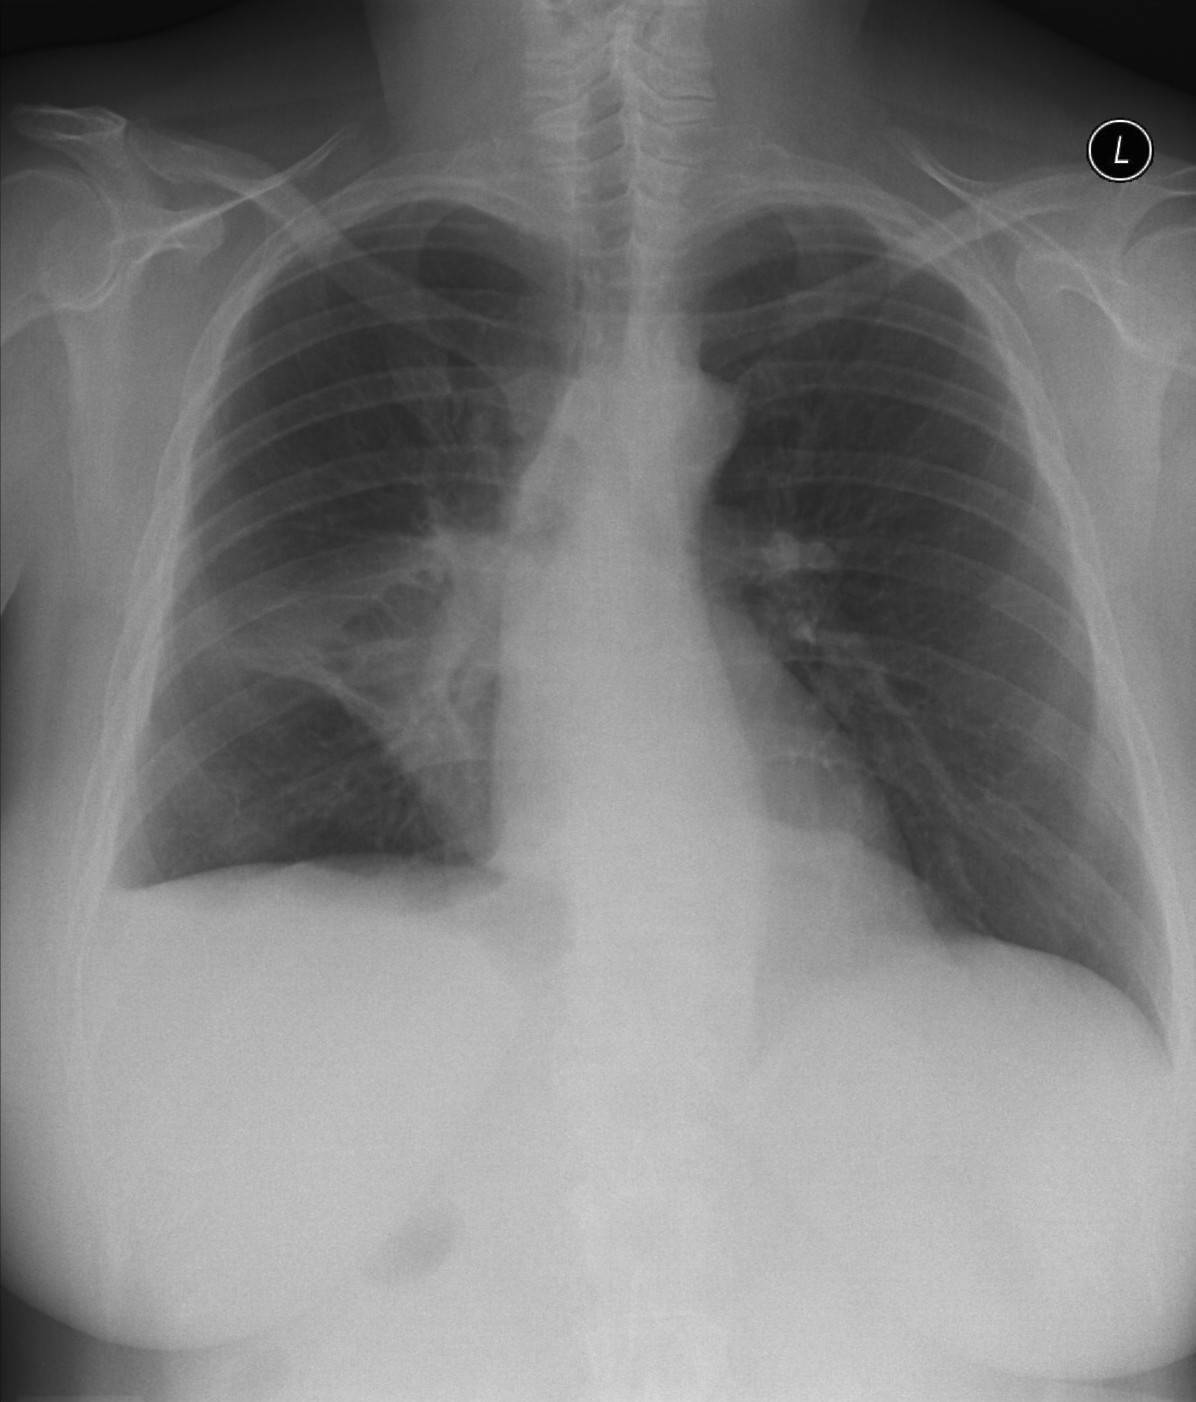

23. Pulmonary metastases, bidirectional (PA and right lateral) plain chest radiograph.

51 year old woman, endometrial carcinoma. Numerous ring shadows bilaterally in basal dominance (max. appr. 12 mm). Left pleural effusion of one finger wide.